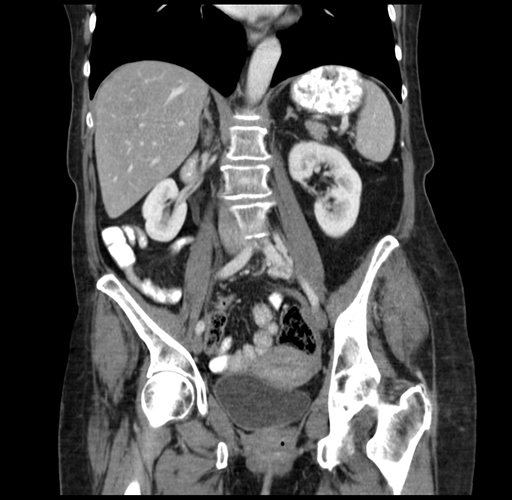

Coronal Venous